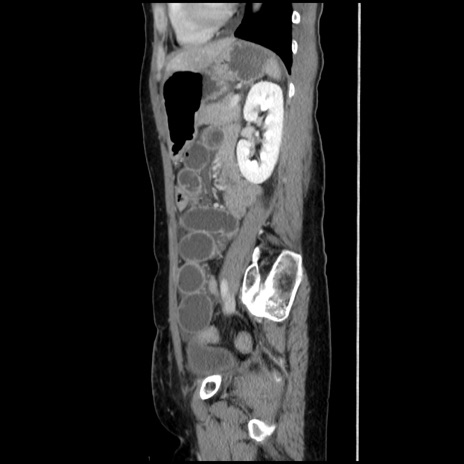

症例32(矢状断像)

【症例】40歳代 女性

【主訴】上腹部痛、嘔気・嘔吐

【現病歴】約9時間前頃から急に上腹部痛、嘔気、嘔吐が出現。改善しないため救急要請。

【既往歴】子宮頚癌(広汎子宮全摘術、放射線療法)、腸閉塞

【身体所見】腹部:平坦、軟、腸雑音亢進、上腹部を中心に腹部全体に圧痛あり。

【データ】WBC 8400、CRP 0.03